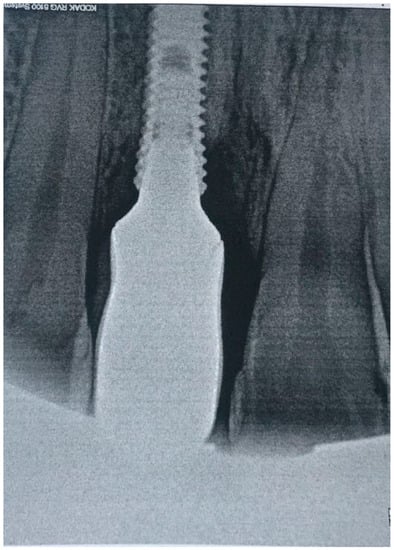

Figure 2.

X-ray of dental implant area before treatment.